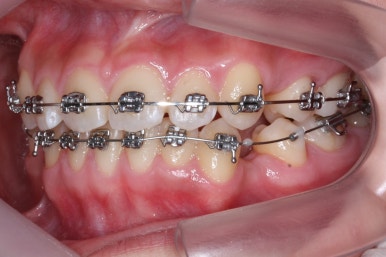

이제는 아래쪽 작은 어금니도 뽑았습니다.

교정치료를 시작한지 3개월 밖에 지나지 않았을 시점인데도 벌써 덧니가 많이 가지런해졌습니다. 치아는 자리만 확보되면 쉽게 가지런해질 수 있습니다.

가지런해지지 않았던 아래 앞니 하나도 금새 가지런해졌습니다.

이제 가지런하게 하는 작업은 거의 종료되었고, 향후의 과정은 남은 이 뽑은 자리를 당겨주어 틈을 없애주면서도 입도 뒤로 좀 넣어주는 것이 되겠습니다.

위아래 아주 단단한 철사로 지탱해주면서 (앞니쪽에 고리가 달린 철사) 앞-뒤 치아를 서로 당겨주면서 이 뽑은 자리를 서서히 없애줍니다.